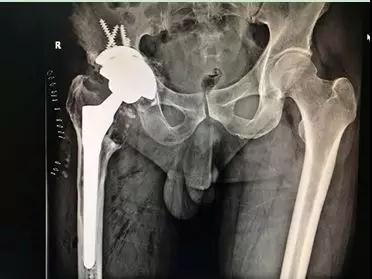

術后X線:骨小梁填充塊重建髖臼骨缺損

通過術后X線可以看出,患者假體安放位置良好,肢體長度恢復,手術成功。目前該患者恢復良好,術后第二天已經可在助行器保護下下床行走。